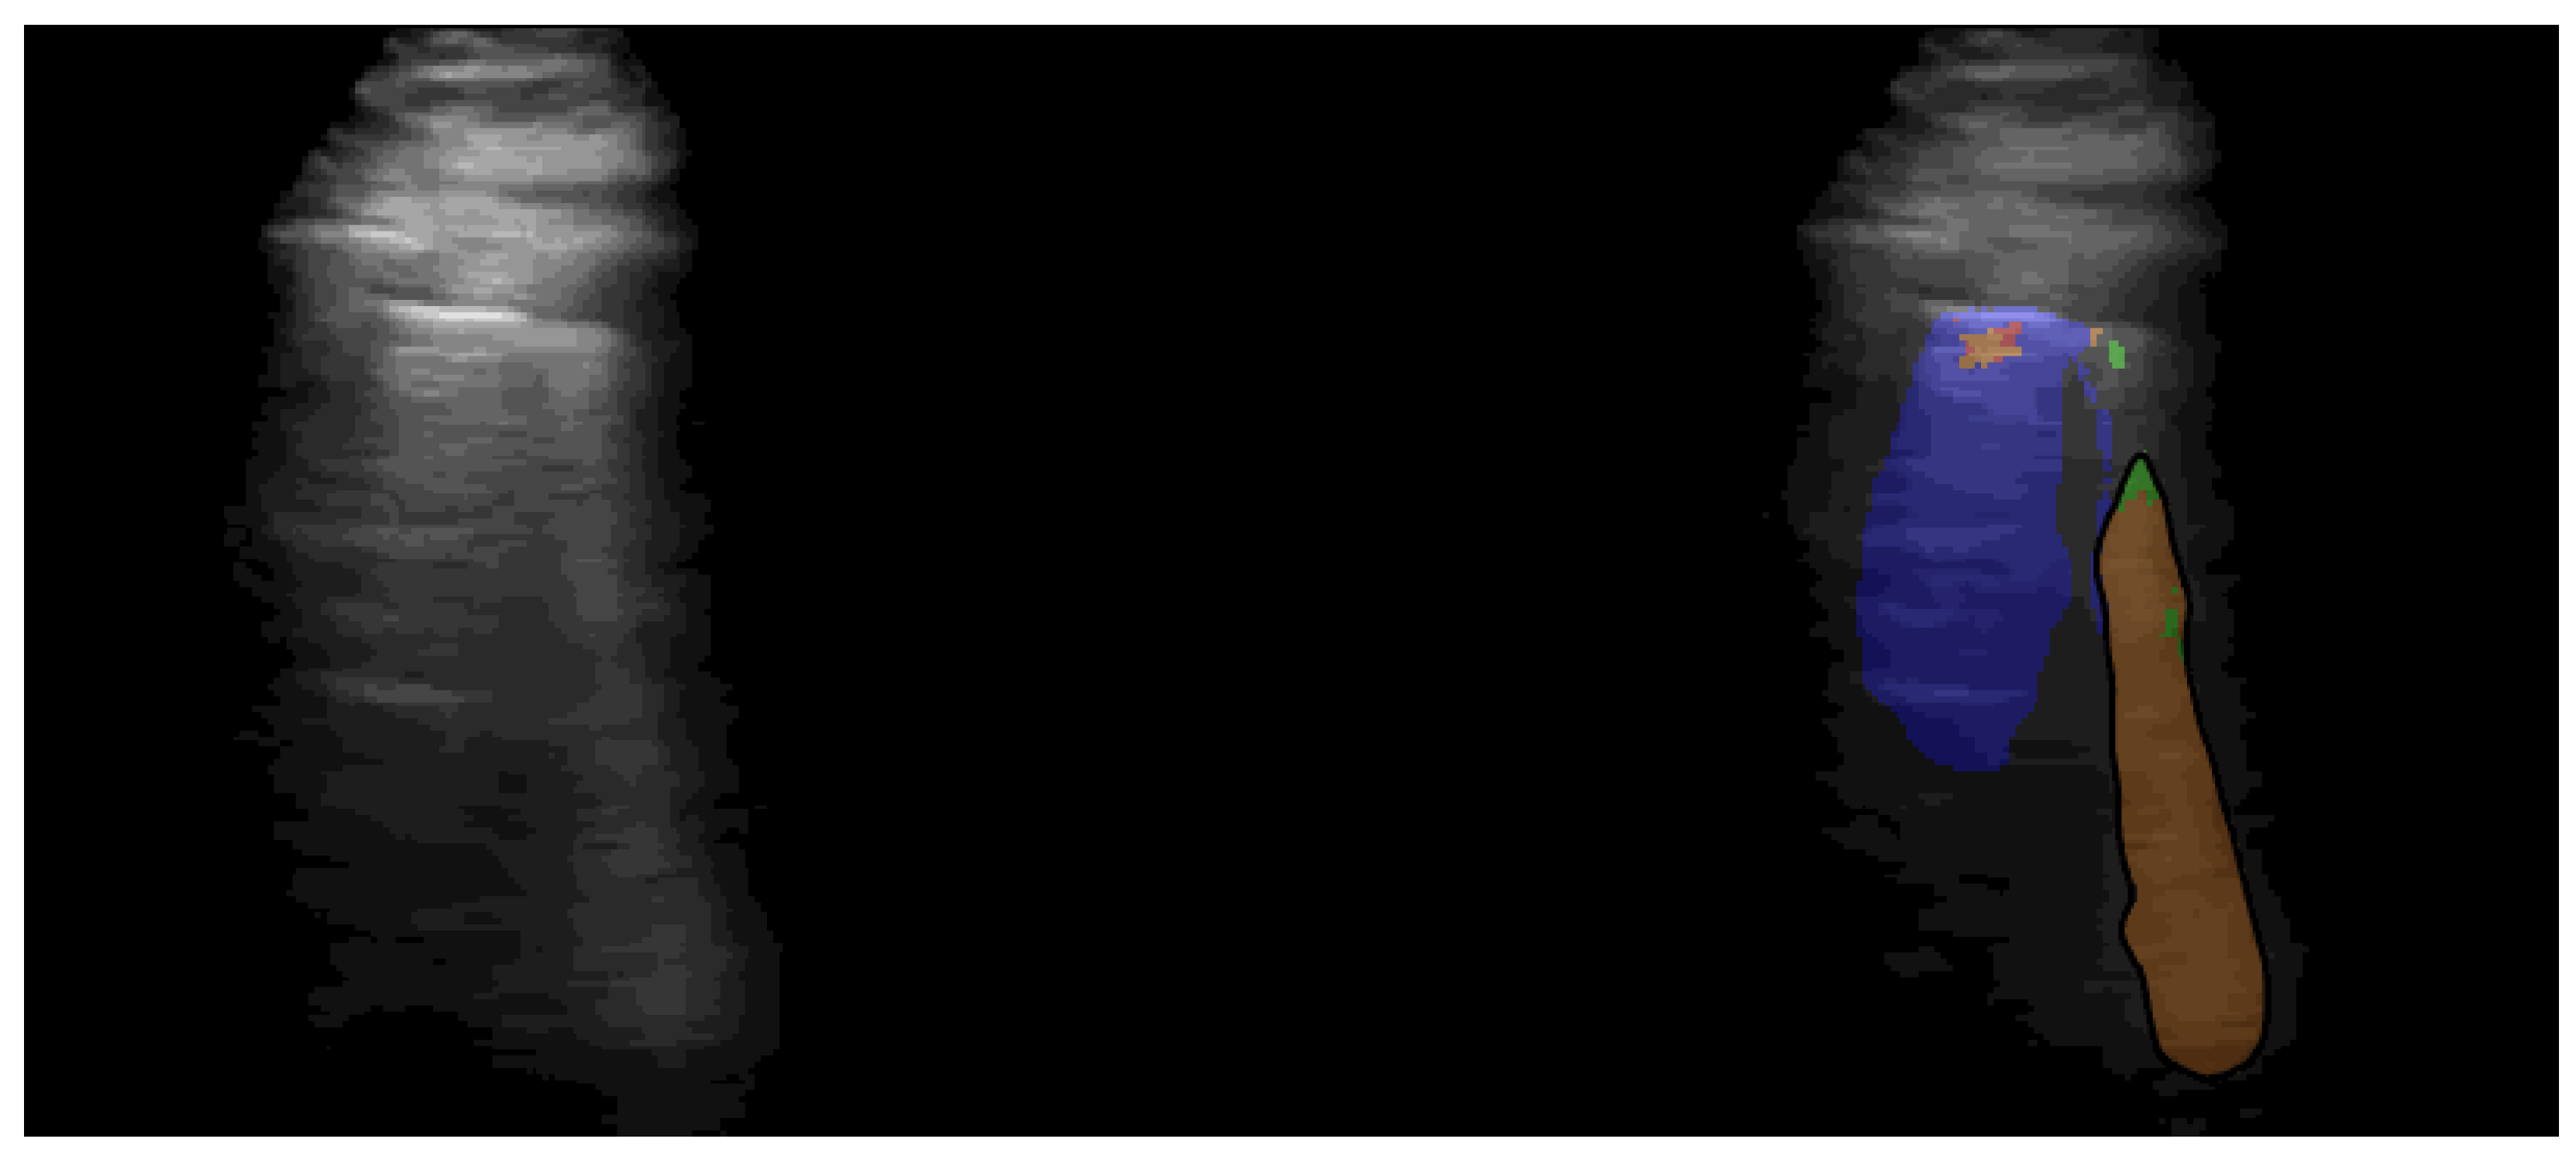

Figure A1 gives an example for the segmented ultrasound image with the model from [57]. In our work the segmented image serves as input to the VGG-Segment model.

Example snapshot from lung segmentation of COVID-19 patient. Left side shows the raw US recording and the right side shows the segmentation method from [57] highlighting the B-line. The images shown on the right were used as input for the VGG-Segment model. Blue, orange and red correspond to signs of healthy, moderate and heavily COVID-19 infected lungs.